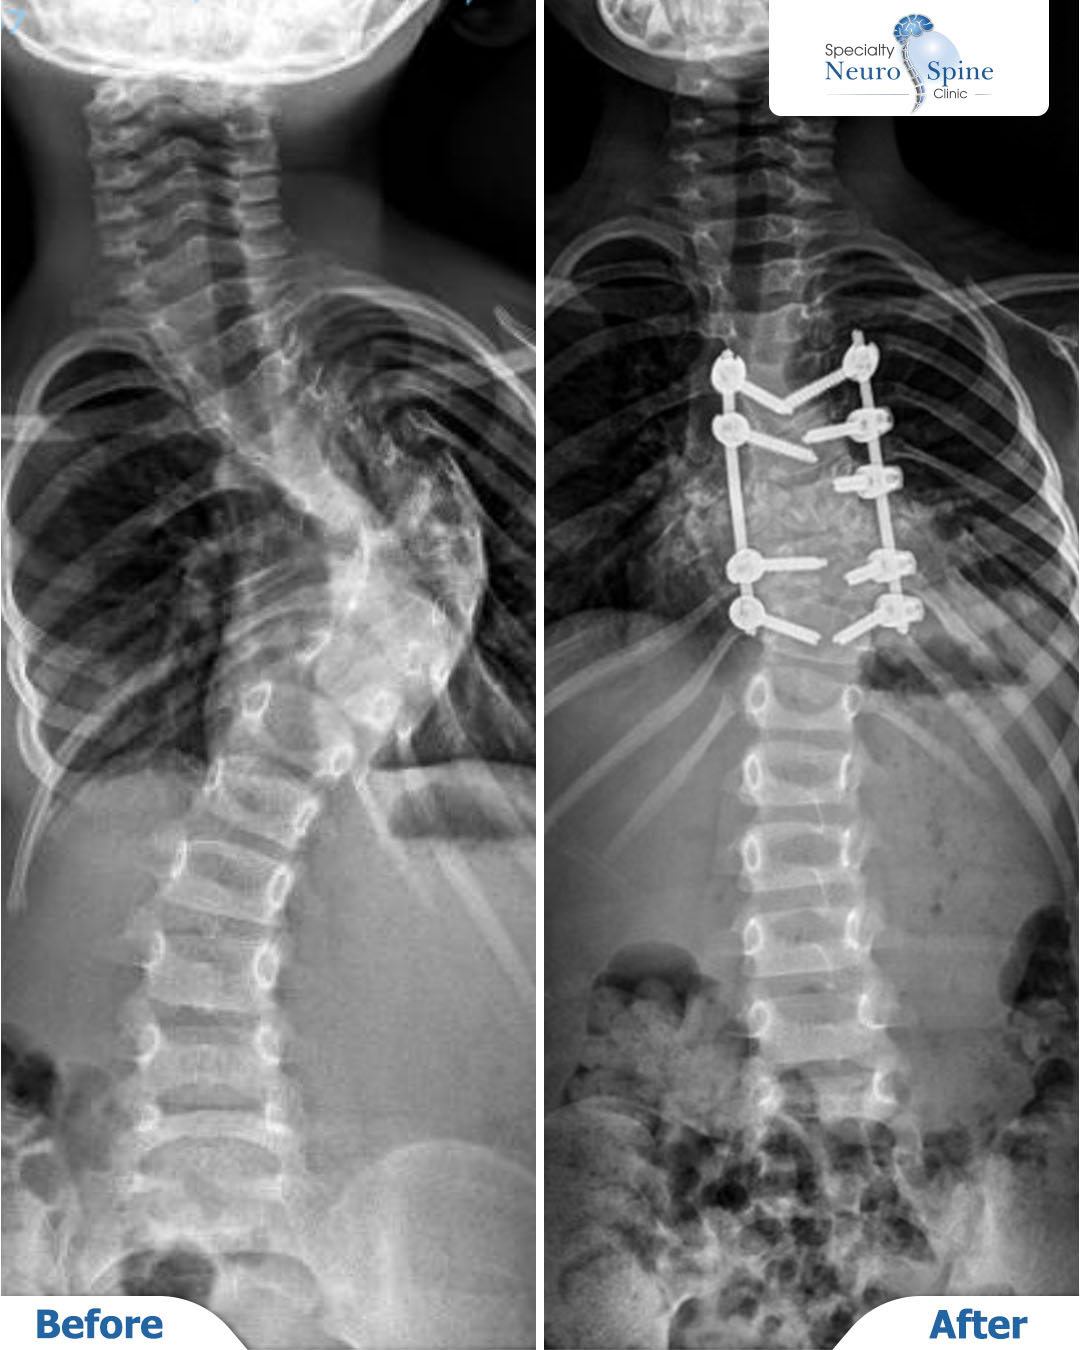

Yousef’s Journey – Minimally Invasive Growing Rods Placement

We were delighted to welcome our brave young patient, Yousef, a 4-year-old from Palestine. Dr. Firas Husban performed a unique minimally invasive spinal procedure to halt the progression of his spinal curvature.

Before-and-after X-rays.

Dr. Firas Husban performed a successful minimally invasive spinal correction surgery, addressing a spinal curvature from the fourth thoracic vertebra (T4) to the fourth lumbar vertebra (L4).

The procedure was completed successfully using advanced medical techniques, with no complications reported.